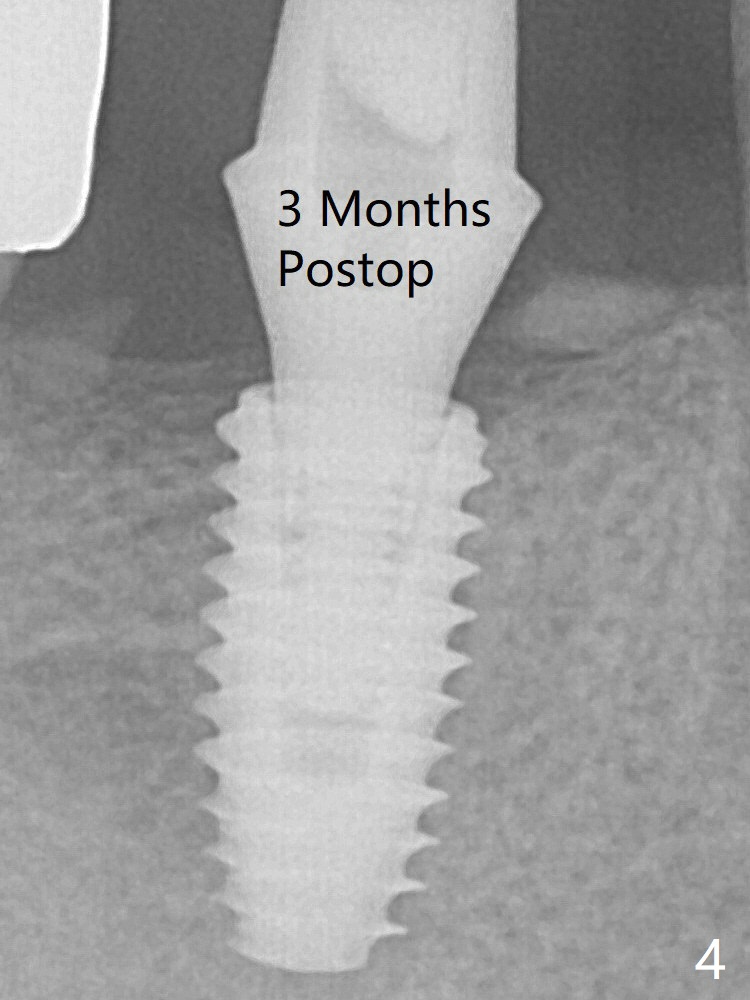

The 5x10 mm implant placed with guide has good trajectory and depth in a timely manner (Fig.3). Since the patient is a heavy bruxer with dislodgement of #30 provisional and #19 abutment screw loosening, a 5.7x4(3) mm cementation abutment is placed immediately so that a splinted provisional is fabricated for #30 and 31 for better retention. However, the gingiva around the implant at #31 is unhealthy 3 months postop (Fig.4). After impression, the provisional at #31 is sectioned without recementation for better oral hygiene.